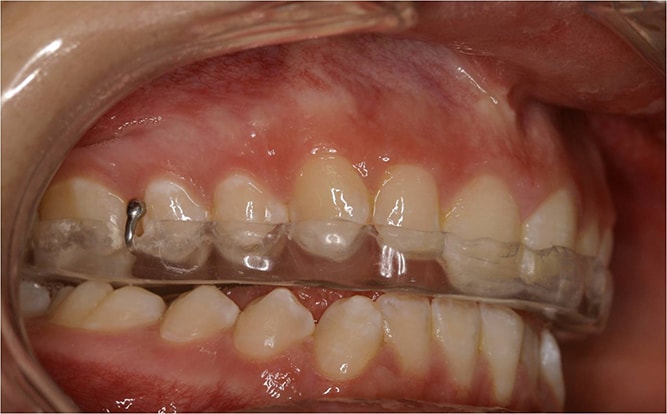

Dezorientációs sín

Általában az alsó fogív fogaira készült átlátszó sínről beszélünk, melynek rágófelszínén átlátszó akrilát van. Súlyosabb állkapocsízületi problémák kezelésénél használjuk. A sín lényege, hogy egyenletes, sima felszínt biztosít a felső fogívvel történő érintkezés során. Ezáltal kiiktatjuk a kóros fogérintkezéseket, relaxáljuk a rágóizmokat, és az ízület a számára legkényelmesebb helyzetbe kerülhet.